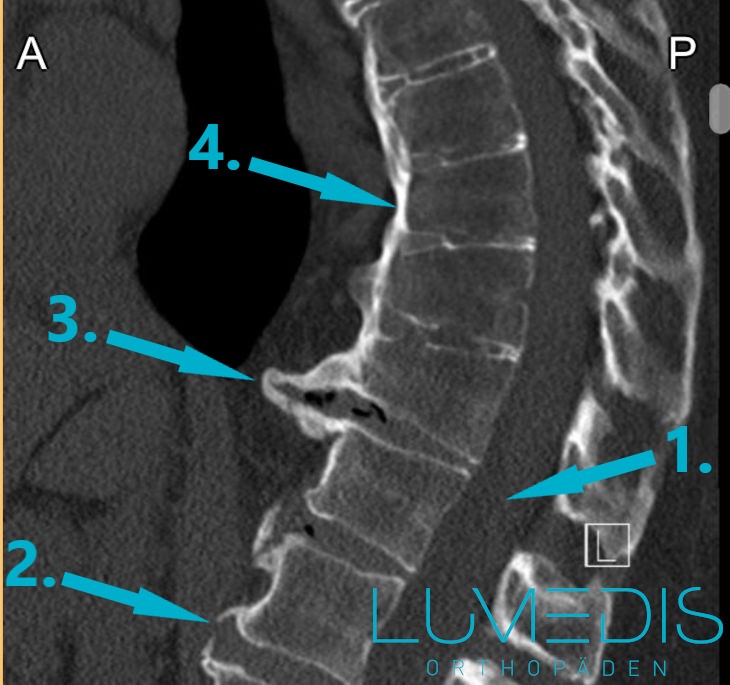

CT Rekonstruktion einer Wirbelsäulenversteifung (Spondylodese)

CT eines Wirbelbruchs der LWS seitlich

CT eines Morbus Forestier